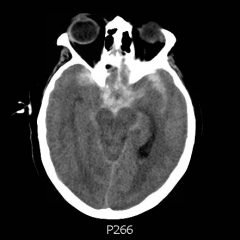

Presentation of Significant Subarachnoid...